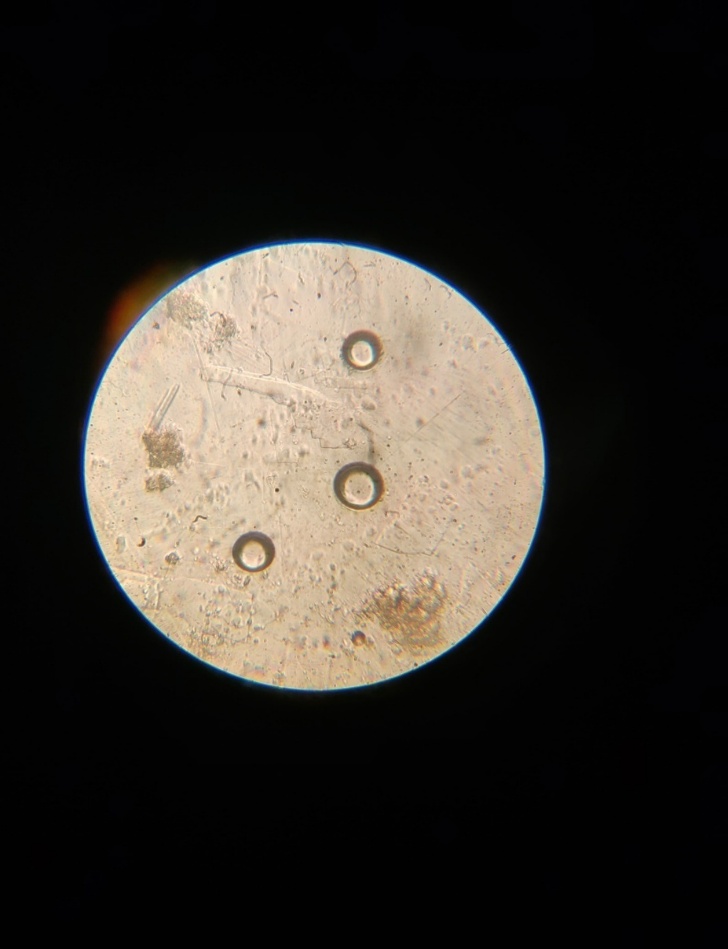

1. Particle size determination 20: -The mean particle size of Dexketoprofen trometamol loaded microsponge was determined using an optical microscope. The microscope was fitted with a stage micrometer to calibrate the eyepiece micrometer. The particle size of formulated cubosome was determined using microscopy. Simple microscope under 100x resolutions was used to determine size of the cubosome. The average particle size was determined using the following formula:

Particle size determination: -The particle size of Dexketoprofen trometamol loaded microsponge ranges from 9-42 µm.

Figure 05:- Optical microscopic image of Dexketoprofen trometamol loaded microsponge